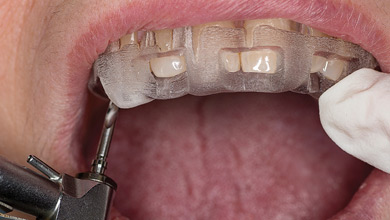

Digital Workflow for Implant Provisionalization in the Aesthetic Zone

Intraoral photo showing frontal view of the patient in MIP with implant healing abutment.

Dental implants have been the recommended treatment of choice as a conservative approach in replacing missing teeth while preserving adjacent tooth structure when compared to fixed dental prostheses.1 The ability of the implant supported crown to replicate natural tooth like emergence profile provides the advantage of achieving higher aesthetic results in the anterior zone.2 Their … Read more